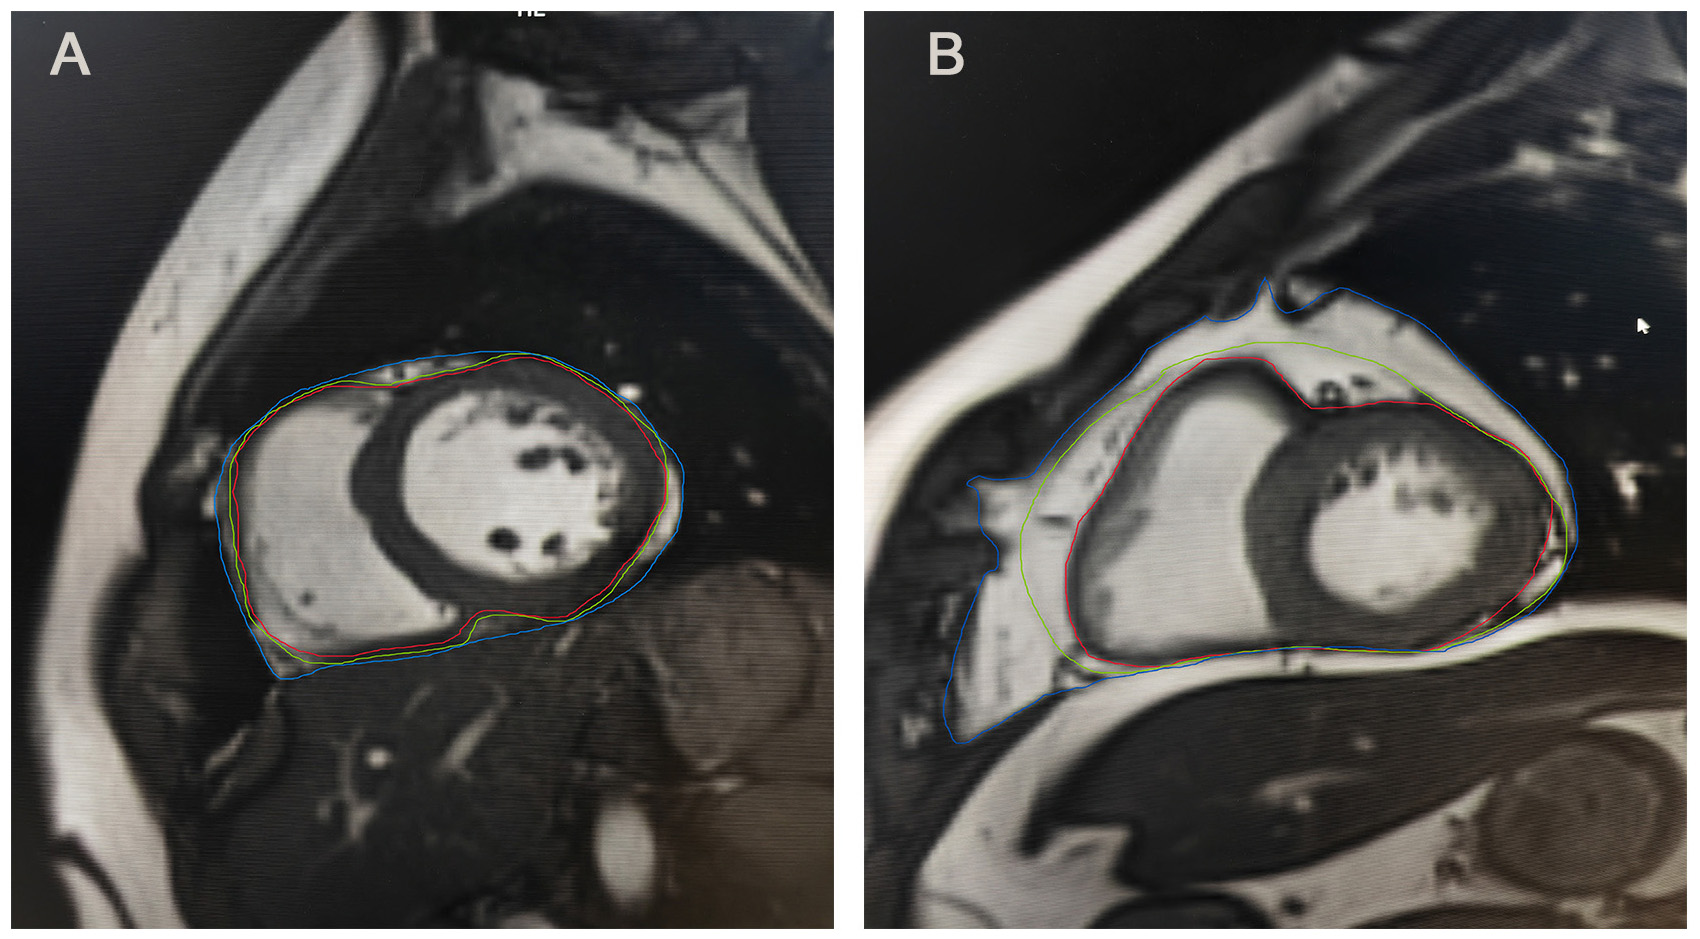

Despite their anatomical proximity, EAT and pericardial adipose tissue (PAT) exhibit fundamental anatomical, embryological, and functional differences. Anatomically, EAT resides between the myocardium and the visceral pericardium, while PAT lies anterior to EAT, situated between the visceral and parietal pericardial layers [32]. Embryologically, EAT adipocytes originate from the splanchnopleuric mesoderm, sharing an origin with mesenteric and omental adipocytes [33]. PAT, in contrast, derives from the primitive thoracic mesenchyme, which differentiates into the parietal pericardium and thoracic wall [33]. Their vascular supply also differs: EAT is supplied by coronary arteries, whereas PAT receives blood from non-coronary sources [33]. Moreover, unlike EAT, PAT lacks a shared microvascular bed with the myocardium [34]. Consequently, EAT and PAT exhibit distinct metabolic and physiological characteristics [35], with EAT demonstrating a stronger association with cardiovascular and metabolic diseases than PAT [36]. In echocardiographic measurements, EAT can be recognized as the echo-free space between the outer wall of the myocardium and the visceral layer of the pericardium [36]. Meanwhile, the PAT thickness can be delineated as the hypoechoic space anterior to the EAT and parietal pericardium, which remains relatively stable and does not deform substantially during the cardiac cycle [36]. On CMR (Fig. 1), EAT is characterized as the adipose tissue between the myocardium and the visceral pericardium, and PAT as adipose tissue external to the parietal pericardium [37].

Fig. 1. Epicardial and pericardial adipose tissue on MRI. (A) Epicardial and pericardial adipose tissue on MRI of individual A. (B) Epicardial and pericardial adipose tissue on MRI of individual B. Individual B exhibited a greater amount of pericardial adipose tissue and epicardial adipose tissue compared to individual A. Epicardial adipose tissue is located between the red and green lines, whereas pericardial adipose tissue is situated between the green and blue lines. MRI, magnetic resonance imaging.